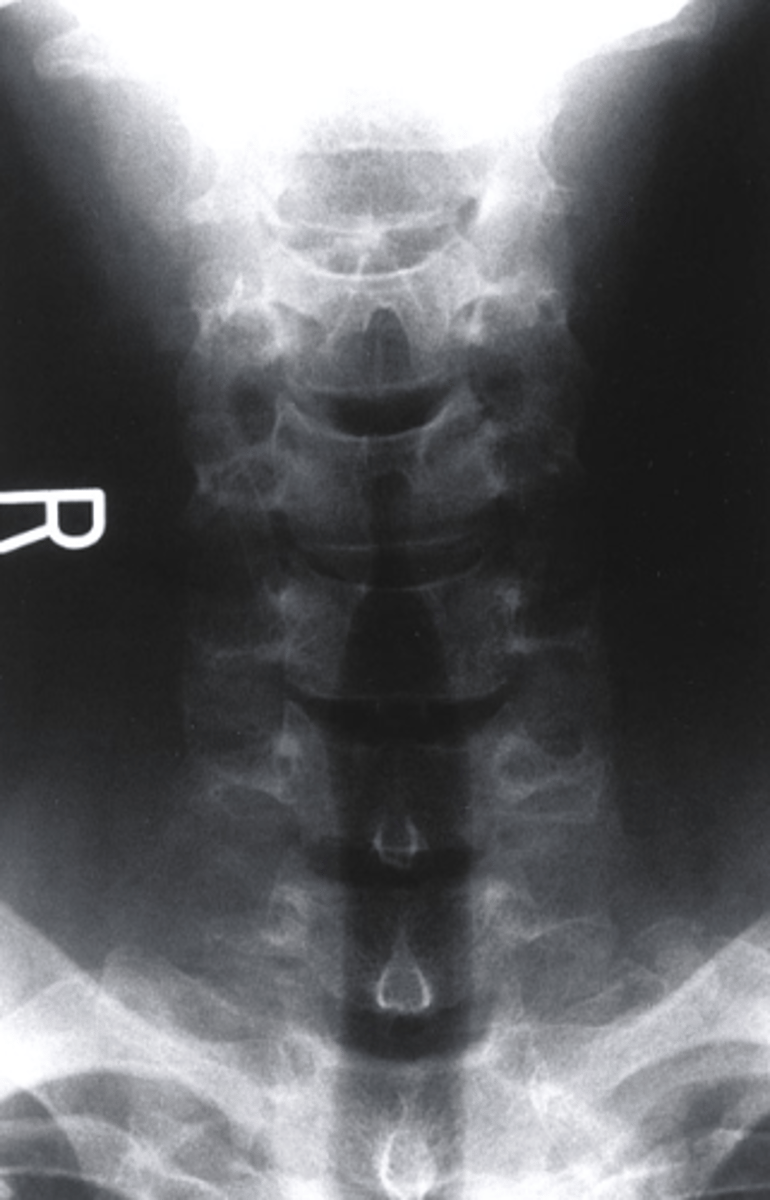

AP Lower C Spine

what view is this?

a. AP Lower C Spine

b. AP Lumbar Spine

c. R oblique

d. L Lateral

what can be seen in an AP lower C-Spine radiograph?

-vertebral bodies of C3-T1

-Spinous processes at some levels

-large transverse process of T1

-First Ribs and costotransverse joints

-clavicles

-air-filled trachea

True or False: You can see the uncinate process in an AP Lower C-Spine Radiograph?

True